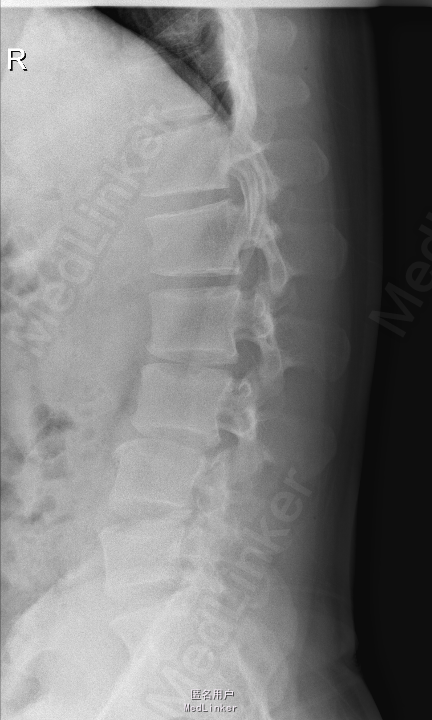

查体:腰部叩痛,腰部活动受限,左侧膝内侧、小腿外侧、内踝、足部感觉减退,右侧小腿、足背感觉减退,屈髋、伸膝、踝背伸肌肌力左侧4级,右侧4-5级,踇背伸、跖屈肌肌力左侧3-4级,右侧4级,双侧膝腱反射+,跟腱反射+,双侧巴氏征阴性,直腿抬高试验左侧40°阳性,右侧阴性。 辅助检查: X-ray:腰椎退行性变,多节段不稳 CT:腰椎间盘突出并椎管狭窄伴钙化,腰2-3,3-4,4-5,腰5骶1 MR:腰椎间盘突出并椎管狭窄,腰2-3,3-4,4-5,腰5骶1 上传受限无法全部上传,见谅

诊断:腰椎间盘突出症并椎管狭窄 处理:1、完善相关辅助检查,明确诊断,有无手术指证; 2、完善手术评估,有无手术禁忌,手术风险及并发症; 3、在全麻下行腰椎后路多节段减压椎间植骨融合内固定术 4、腰2-3,腰3-4行开窗减压,腰4-5,腰5-骶1行椎间Cage植骨融合